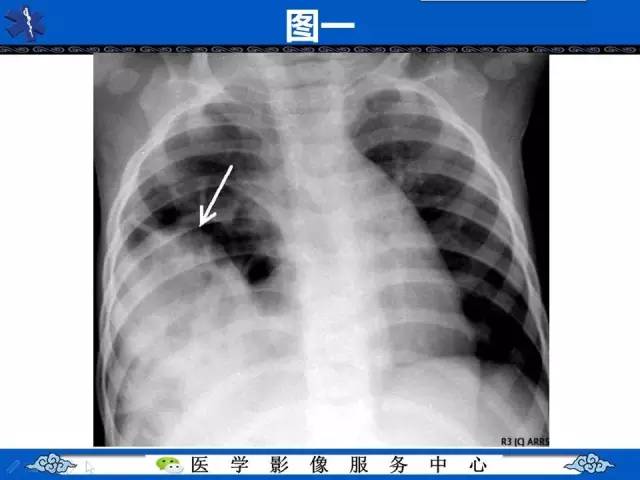

圆锥面包征——膈肌破裂

【影像征象】圆锥面包征——膈肌破裂